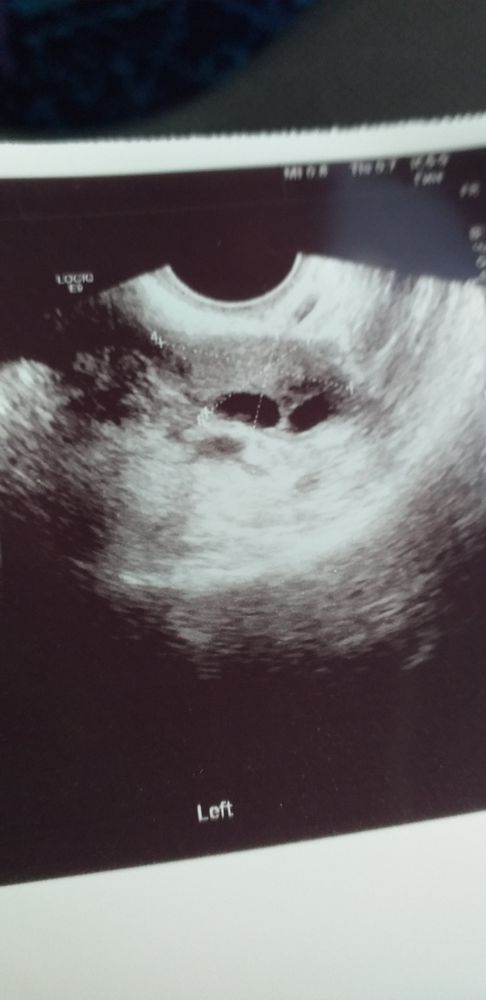

Это яичник с фолликулами. А в чем ваш вопрос

Ангелина, второй раз за месяц мазня вот и думаю может это О так себя ведёт

Любовь Клепикова, мзаня это либо: недостаток эстрагенов, гиперплазия, аденомиоз, эндомеириоз. Ну не как не овуляция....

Может быть овуляция на 26!-27дц? Когда Была/будет О? График бт